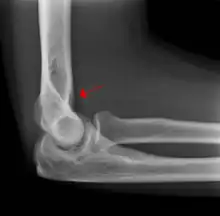

A subtle radial head fracture with associated positive sail sign

The fat pad sign, also known as the sail sign, is a potential finding on elbow radiography which suggests a fracture of one or more bones at the elbow. It is may indicate an occult fracture that is not directly visible. Its name derives from the fact that it has the shape of a spinnaker (sail).[1] It is caused by displacement of the fat pad around the elbow joint. Both anterior and posterior fat pad signs exist, and both can be found on the same X-ray.

In children, a posterior fat pad sign suggests a condylar fracture of the humerus. In adults it suggests a radial head fracture.

The fat pad sign is invaluable in assessing for the presence of an intra-articular fracture of the elbow. An anterior fat pad is often normal. However a posterior fat pad seen on a lateral x-ray of the elbow is always abnormal. The patient will be unable to flex their elbow and requires orthopaedic input.[2]